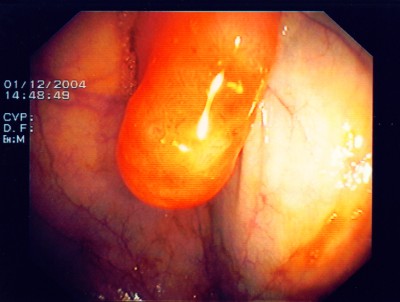

Nach einem speziellen kombinierten Manöver (laparaskopisch gestützte Koloskopie - gleichzeitige Bauch- und Darmspiegelung), gelingt es, den Polyp weit im Gesunden mit einem speziellen Klammernahtgerät zu entfernen, wobei die hier abgebildete Klammernahtreihe zurück bleibt. Der Eingriff erfolgt - wie gesagt - in so genannter Schlüssellochtechnik, aber auch mit unterstützender Darmspiegelung.